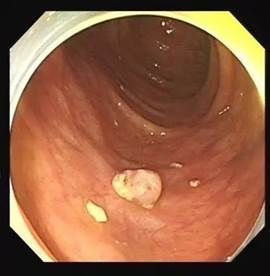

直肠癌可以摸到肿块质地较硬,表面高低不平或呈菜花样,有脓液、坏死组织及暗红色的血液,并感觉肠腔狭窄,指套上也染有暗红色血液。

直肠息肉可触及质软且可推移的肿块,指套上常染血,色鲜红。